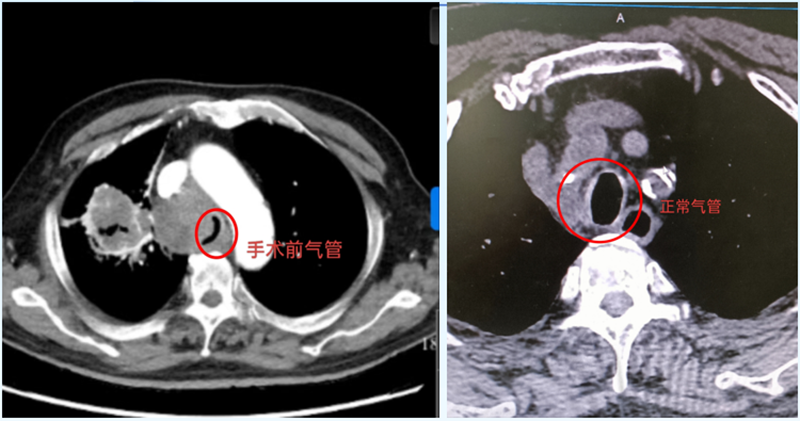

CT影像揭開了兇險:右肺門區(qū)的惡性腫瘤已悄然“逼近”氣道,把氣管擠得只剩一條窄縫?!熬拖裼檬制×瞬弊樱瑲飧疚贿M去!”醫(yī)生快速判斷,立即展開抗炎、平喘治療,暫時為于大爺“松了綁”??烧l也沒想到,這場“呼吸保衛(wèi)戰(zhàn)”才剛剛開始。

次日凌晨,于大爺?shù)暮粑蝗辉俅巍案婕薄?。監(jiān)護儀上的血氧飽和度直線下降,他張著嘴卻發(fā)不出聲音,仿佛有只無形的手死死扼住喉嚨。呼吸內(nèi)鏡中心主任劉傳偉聞訊趕來,盯著影像片眉頭緊鎖:“腫瘤壓迫氣管成了‘細線’,必須立刻撐開氣道,否有生命危險!

支氣管鏡鏡頭下,氣道中下段被瘤體壓得只剩發(fā)絲寬,粘痰像“絆腳石”堵在狹窄處。劉傳偉主任穩(wěn)住鏡身,助手精準(zhǔn)遞過支架推送器——“3、2、1,釋放!”隨著“咔嗒”一聲輕響,支架如“微型橋梁”撐開塌陷的氣管。